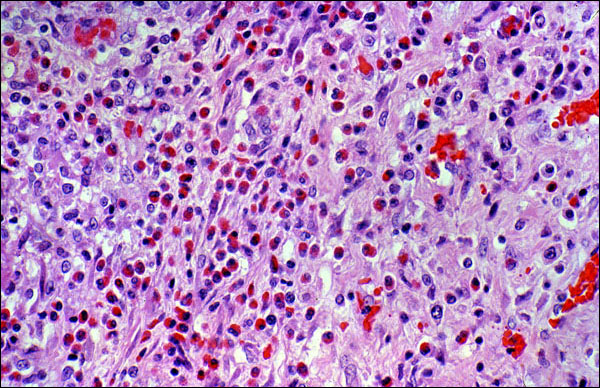

Eosinophil in tissue

This is a relatively low power photomicrograph of a section of tissue that contains large numbers of eosinophils. This might be an inflammatory reation that is associated with the presence of a parasite. Even at this low level of magnification, it is readily possible to identify these leukocytes as eosinophils, because of their large, bright red granules.